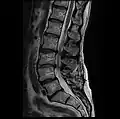

MRI lumbar spine with degeneration, post-hemilaminectomy L4-5 (sagittal T1 FSE)